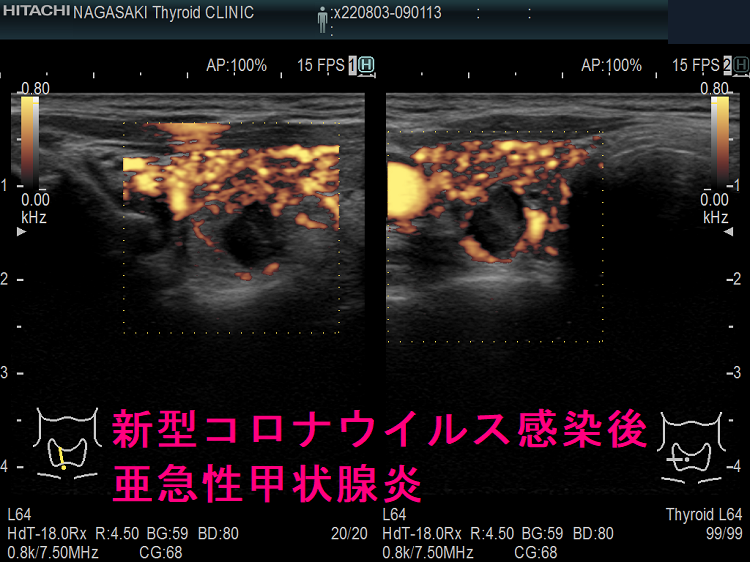

以下は、長崎甲状腺クリニック(大阪)の自験例です。

長崎甲状腺クリニック(大阪)の自験例

急性期